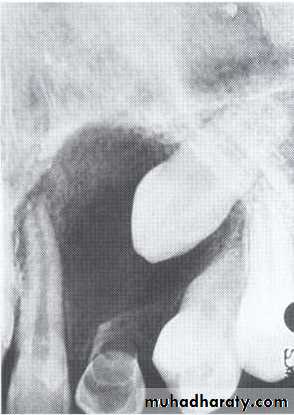

Dentigerous CystIt forms around the crown of an unerupted or supernumerary tooth at CEJ.

Some dentigerous cysts are eccentric, developing from the lateral aspect of the follicle so that they occupy an area beside the crown instead of above the crown.

It displace and resorb adjacent teeth.

It commonly displaces the associated tooth

in an apical direction.